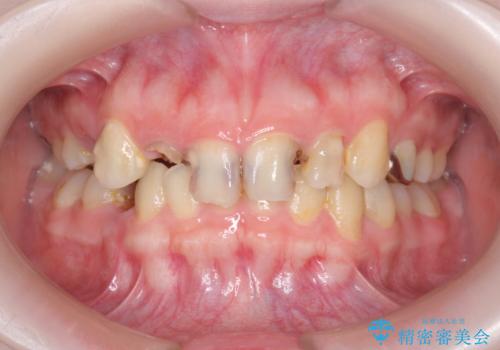

多発した前歯の重度虫歯治療

- 放置した虫歯の歯がボロボロになってしまい治療を希望され来院されました。

残根状態の歯、神経まで虫歯が達し失活した歯、歯肉縁下まで及んだ虫歯が多数認められます。